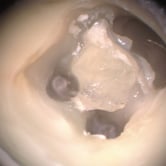

Perforación Radicular

Una perforación radicular es una abertura anormal en la raíz del diente, generalmente debido a un procedimiento dental fallido o una caries profunda.

Los pacientes pueden sentir dolor y notar hinchazón en la encía.

El tratamiento incluye la reparación de la perforación y el tratamiento de conducto. Es crucial reparar la perforación para evitar una infección.